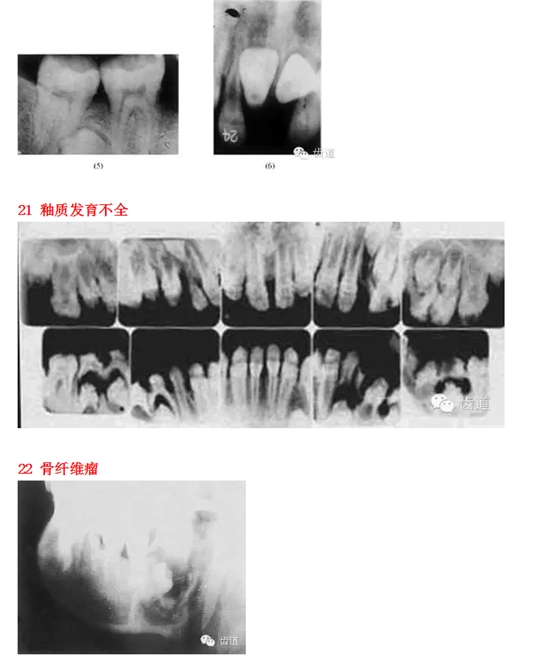

26種口腔病變X光片